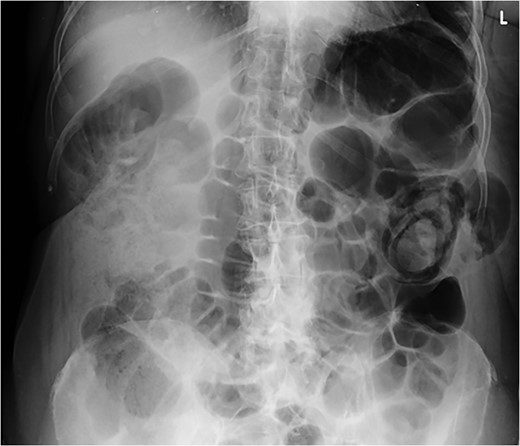

On examination, there was a 15 cm, irreducible, mildly tender lump in the left superior lumbar triangle, in the region of previous lipoma excision. There were audible bowel sounds on auscultation of the lump. No other swellings of the abdominal wall were identified and the patient was not known to have any hernias. Abdominal radiograph revealed faecal loading in the ascending colon with dilated large bowel loops (Fig. 2). Subsequent computed tomography (CT) scan showed a left superior lumbar triangle hernia containing a loop of colon (Fig. 3) with dilated large bowel proximal to this, in keeping with obstruction.

Abdominal supine plain radiograph showing faecal loading in ascending colon and dilated large bowel loops in a 72-year-old woman diagnosed with large bowel obstruction secondary to left sided superior lumbar triangle hernia.